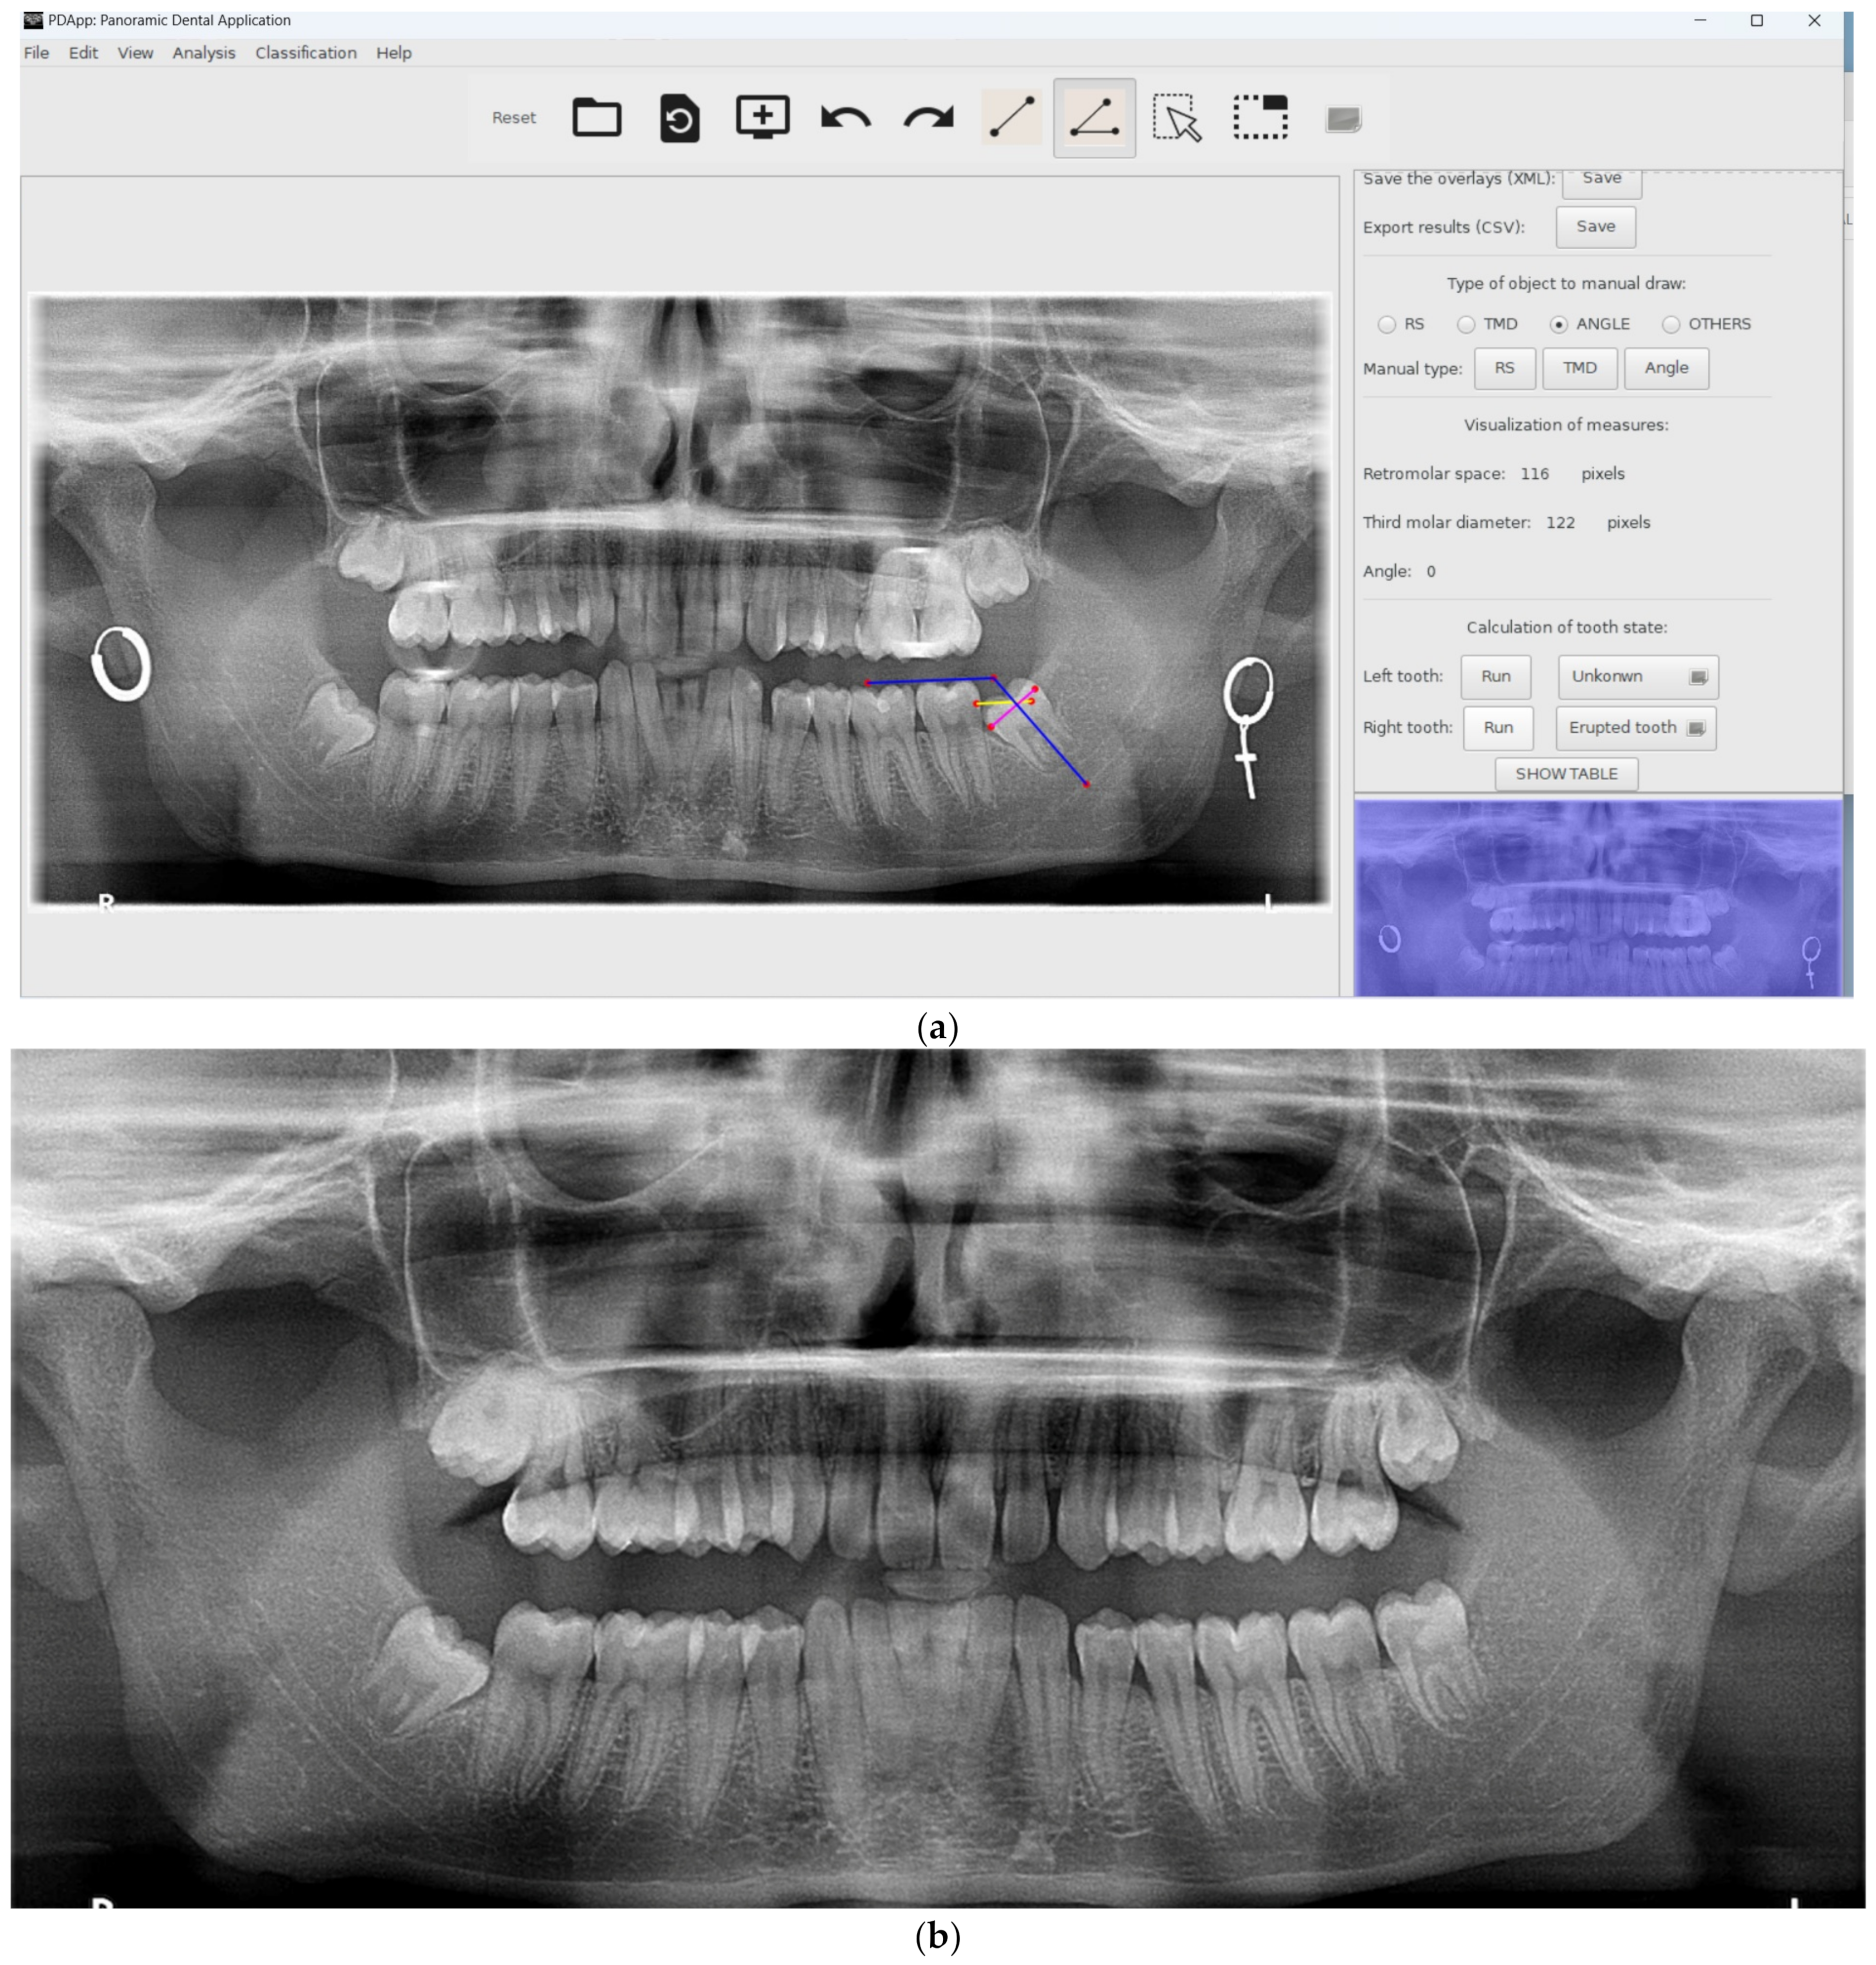

- Provide a friendly GUI to interactively work with radiological images and draw lines and angles for analysis.

- Measure lines and angles in the images.

- Manually draw the retromolar space, the third molar diameter, and the angle for each third molar.

- Automatically measure the distances and angles.

- Automatically classify the third molars.